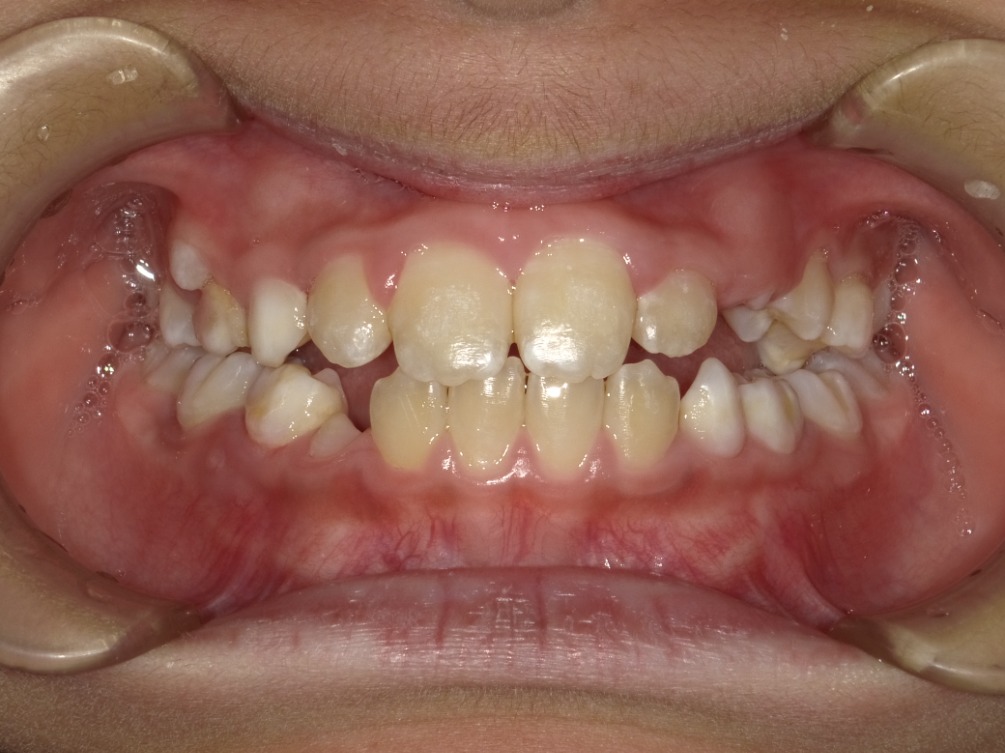

正面

| 治療内容 | インビザライン・ファースト |

|---|---|

| 治療詳細 | 反対咬合や叢生、開咬を整えるために、歯の表面にアタッチメント(白い突起)をつけました。 また、顎間ゴムと呼ばれる引っ掛けるゴムの補助装置も用いて治療を行いました。 |

| 患者情報 | 10代 男性 予防矯正から移行 |

| 主訴 | 受け口 |